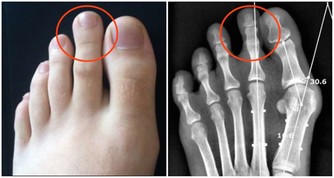

A先生做了全身健康檢查之後,被診斷出患有高血壓。

為了給他最正確的建議,我先幫他量了血壓,結果為168/98 mmHg。

這個數值確實不算低。

不過,A先生過去沒有心臟或腎臟方面的病史,身材也不屬於肥胖型,重要的是生活作息相當正常。